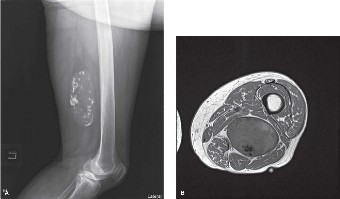

An 18-year-old male presents to your office with pain in his lower right leg and an enlarging mass over the a…